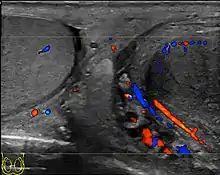

The US appearance of varicocele consists of multiple, hypoechoic, serpiginous, tubular like structures of varying sizes larger than 2 mm in diameter that is usually best visualized superior or lateral to the testis [Fig. 27a]. Color flow and duplex Doppler US optimized for low-flow velocities help confirm the venous flow pattern, with phasic variation and retrograde filling during a Valsalva's maneuver [Fig. 27b]. Intratesticular varicocele may appear as a vague hypoechoic area in the testis or mimics tubular ectasia. With color Doppler, this intratesticular hypoechoic area also showed reflux of vascular flow during Valsalva's maneuver [Fig. 28].